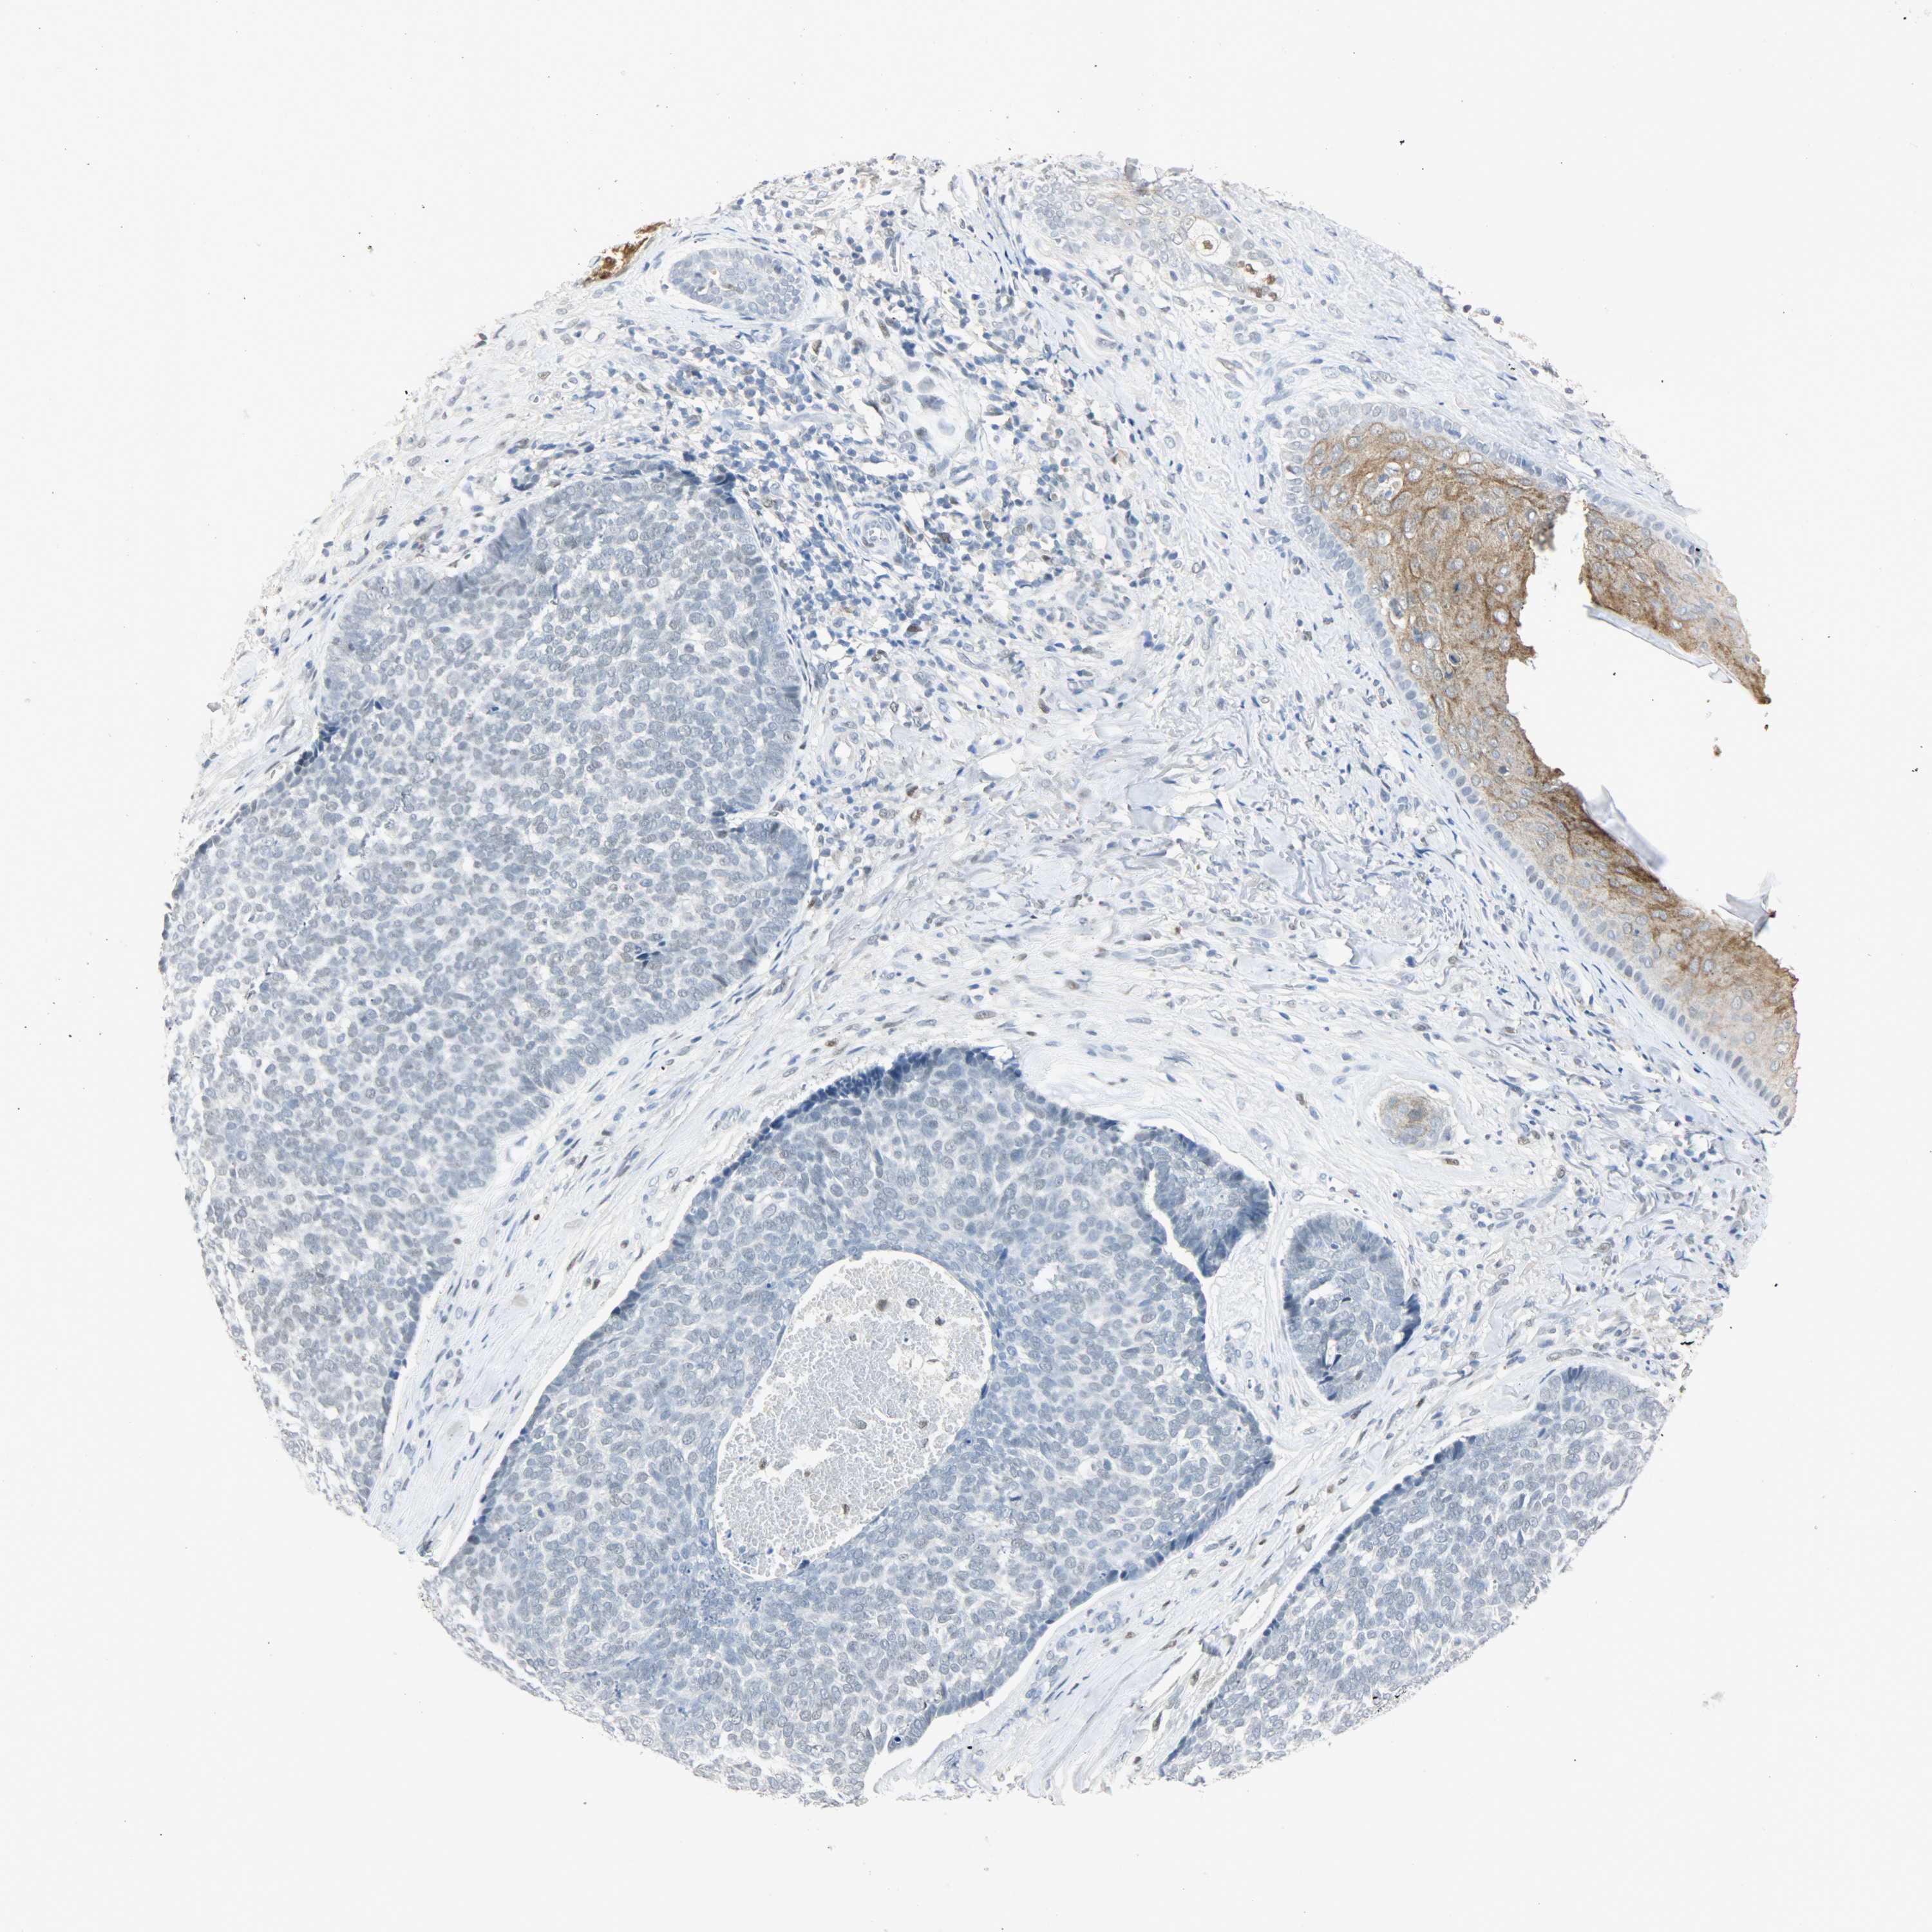

SKIN CANCER - Protein expressioni

A mouse-over function shows sample information and annotation data. Click on an image to view it in a full screen mode. Samples can be filtered based on level of antibody staining by selecting one or several of the following categories: high, medium, low and not detected. The assay and annotation is described here.

Antibody stainingi

Antibody staining in the annotated cell types in the current human tissue is reported as not detected, low, medium, or high, based on conventional immunohistochemistry profiling in selected tissues. This score is based on the combination of the staining intensity and fraction of stained cells.

Each image is clickable and will lead to virtual microscopy that enables deeper exploration of all samples and also displays staining intensity scores, fraction scores and subcellular localization as well as patient and tissue information for each sample.

Antibody CAB004282

Medium

Low

Not detected

Intensity

Weak

Negative

Quantity

<25%

None

Location

Basal cell carcinoma